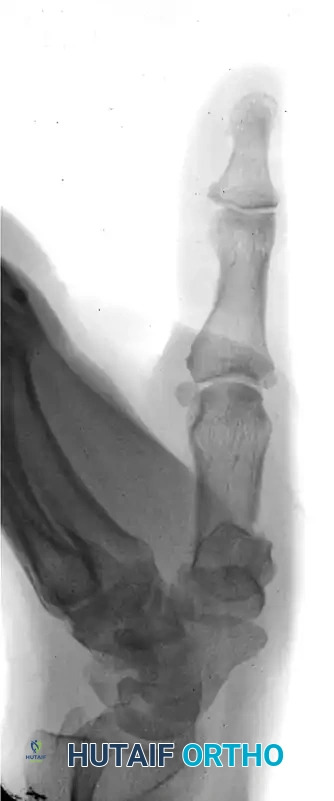

The following sequence illustrates the progression from injury to successful closed reduction and K-wire fixation into the trapezium: